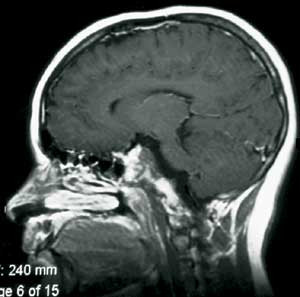

Pasient 1. Ni år gammel pike, født til termin, upåfallende psykomotorisk utvikling. Fra sju års alder klaget hun periodevis over svie/kløe i begge øynene og dobbeltsyn. Hun ble da bredt utredet uten resultat. Symptomene gikk delvis tilbake, men påfølgende år tilkom økende symptomer og man påviste da en bilateral abducensparese. Ny bildediagnostikk avslørte nå en stor ekspansiv prosess utgående fra clivus med affeksjon av pons, mest forenlig med et clivuskordom (fig 2a).

Det postoperative forløpet var meget tilfredsstillende. Hun kunne mobiliseres første dag etter inngrepet uten nye nevrologiske utfall. En postoperativ MR avslørte en liten resttumor (fig 2b). Hun ble derfor henvist og behandlet ved Stråleknivenheten, Nevrokirurgisk avdeling, Haukeland Universitetssykehus. Påfølgende år har hennes dobbeltsyn vært i jevn bedring. MR-kontroller har vist at resttumor er i regresjon.

Pasienten ble henvist til Nevrokirurgisk avdeling, Rikshospitalet for vurdering med tanke på ytterligere kirurgi. Det forelå nå imidlertid en betydelig tumordestruksjon og invasjon i clivus av solide tumorkomponenter og ny cyste posterokaudalt mot 3. ventrikkel/hypothalamus og pons (fig 3a). Klinisk var pasienten også i meget rask forverring og hadde preoperativt redusert bevissthet, sløvet tale, ustø gange og urininkontinens.

Pasienten er ved tremånederskontroll betydelig restituert og har kun en mindre ekstremitetsparese. Som før den siste operasjonen er han blind og fullstendig hormonsubstituert. Postoperativ MR-undersøkelse viser ikke tegn til resttumor (fig 3b).